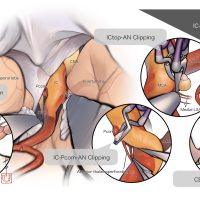

術後イラストシリーズ